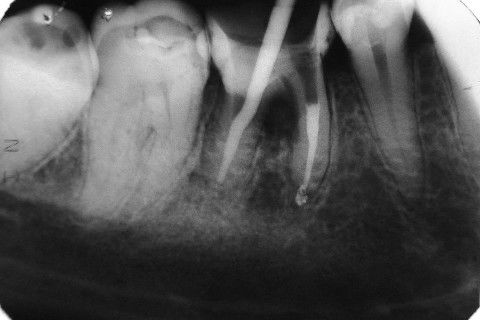

Retratamento de Canal, Tratamento de Perfuração, Restauração Provisória com Resina, Núcleo e Provisório.

RETRATAMENTO DE CANAL, TRATAMENTO DE PERFURAÇÃO, RESTAURAÇÃO PROVISÓRIA COM RESINA, NUCLEO E PROVISÓRIO.